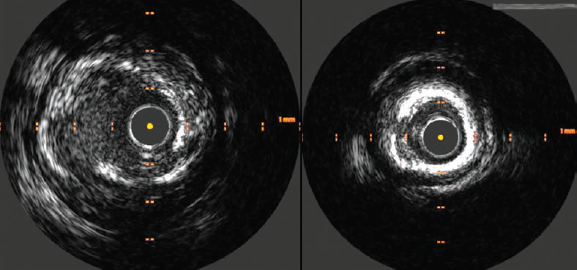

A 6 French right radial access was obtained and the left main coronary artery (LMCA) was cannulated. The first diagonal branch was wired and the LAD was wired with a second wire. Pre-dilation from the mid LAD back into the LMCA was performed with 2.0 x 20 mm semicompliant balloon. Intravascular ultrasound (IVUS) was then performed with the Refinity short-tip rotational IVUS catheter (Philips) in the mid LAD into the LMCA, and demonstrated fibrocalcific plaque with segments of circumferential calcium (Figure 2). The distal reference diameter was measured as 3.4 mm in the LAD and proximal reference diameter as 4.2 mm in the LMCA (Figure 3).